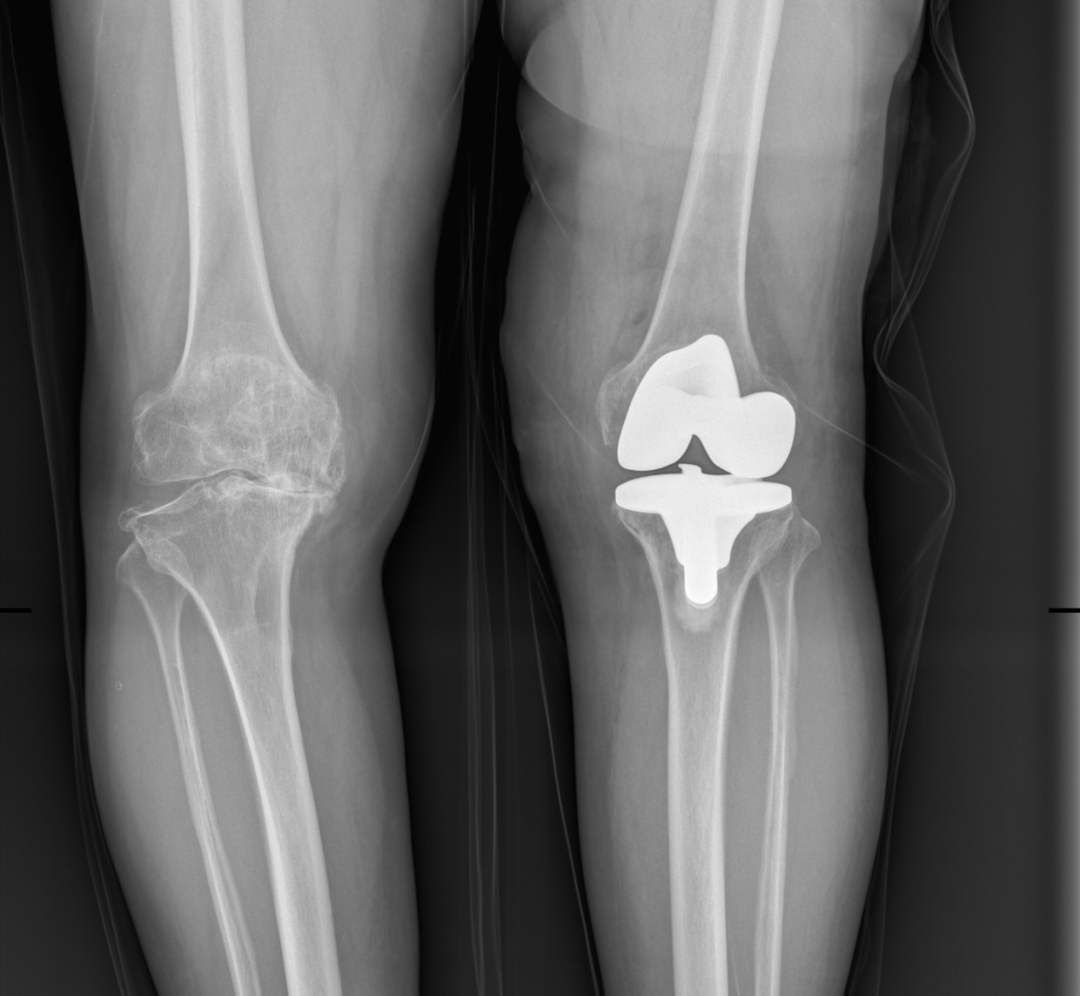

第二次右侧人工全膝关节置换术后